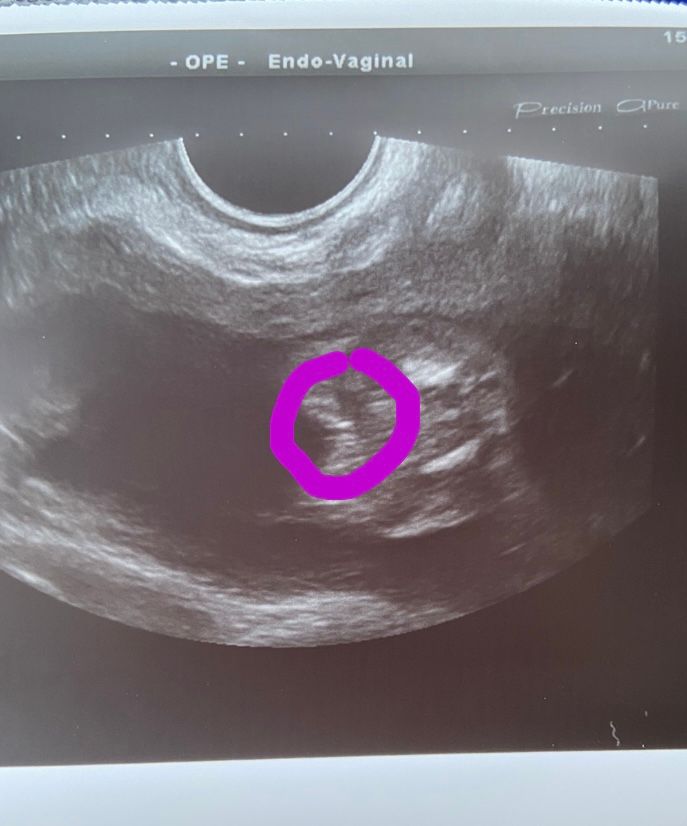

Дайте розовые краски!🙏🙏🙏

Как что делать? Любить, целовать, платья и бантики покупать 🥰 Делала узи в 16 недель, такая же картинка была, так что не отрастет уже😁

Мне тоже в 16 недель определили дочку🤗Сейчас почти 32 - ничего не отросло😅😅